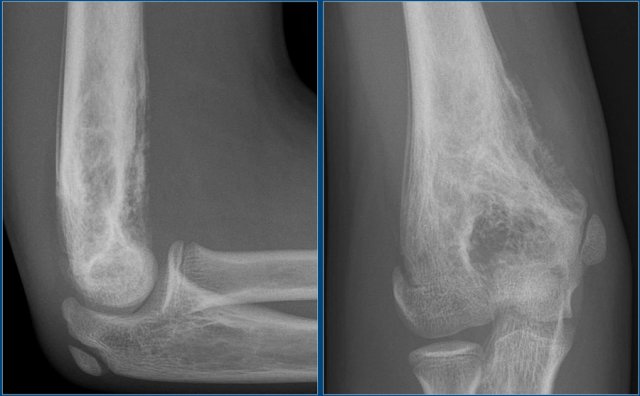

Here images of a 33-year old male with a diaphyseal eccentric sharply defined lytic lesion predominantly located in the cortical bone.

CT shows the cortical origin with thin peripheral rim in this patients with hyperparathyroidism.

Diagnosis: Brown tumor.